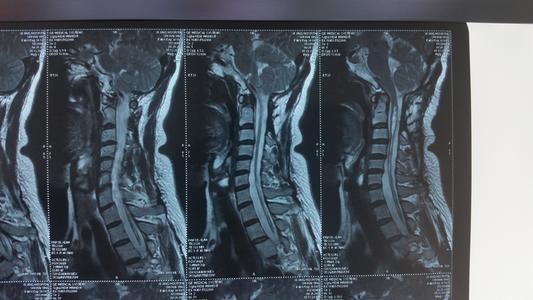

此外,脊髓空洞術(shù)后還應(yīng)注意觀(guān)察患者感覺(jué)平面恢復(fù)情況,出院前及術(shù)后3月復(fù)查核磁共振,復(fù)查。